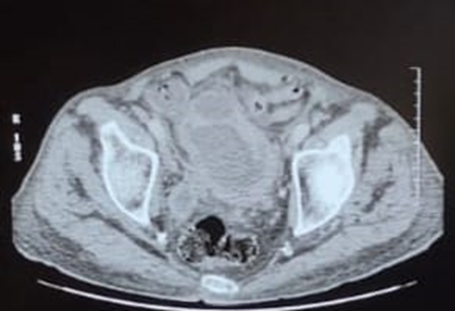

A contrast-enhanced CT scan demonstrated circumferential and irregular bladder wall thickening (maximum thickness 24 mm) involving a diverticular bladder dome measuring 34 × 25 mm. The diverticulum exerted a mass effect on an adjacent ileal loop, resulting in subtotal luminal occlusion and upstream small bowel distension with air-fluid levels (31 mm maximum diameter). A “pearl sign” was visible at the site of obstruction.

The findings were consistent with small bowel mechanical obstruction secondary to mass effect from a diverticulum infiltrated by urothelial carcinoma.

Figure 2. Abdominal CT scan showing small bowel distension with air-fluid levels, suggestive of mechanical obstruction secondary to extrinsic compression.